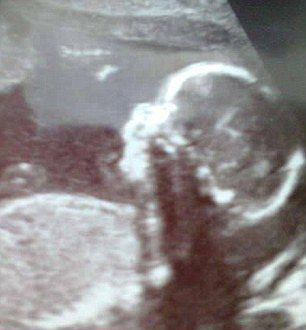

英婴儿神似匹诺曹 脑袋长到鼻子上(组图)

尽管医生在20周时提醒了母亲孩子患有缺陷的事实,但在孩子出生时母亲Amy Poole仍然被吓了一跳。

原标题:英国婴儿天生缺陷神似匹诺曹

英国婴儿天生缺陷神似匹诺曹【组图】